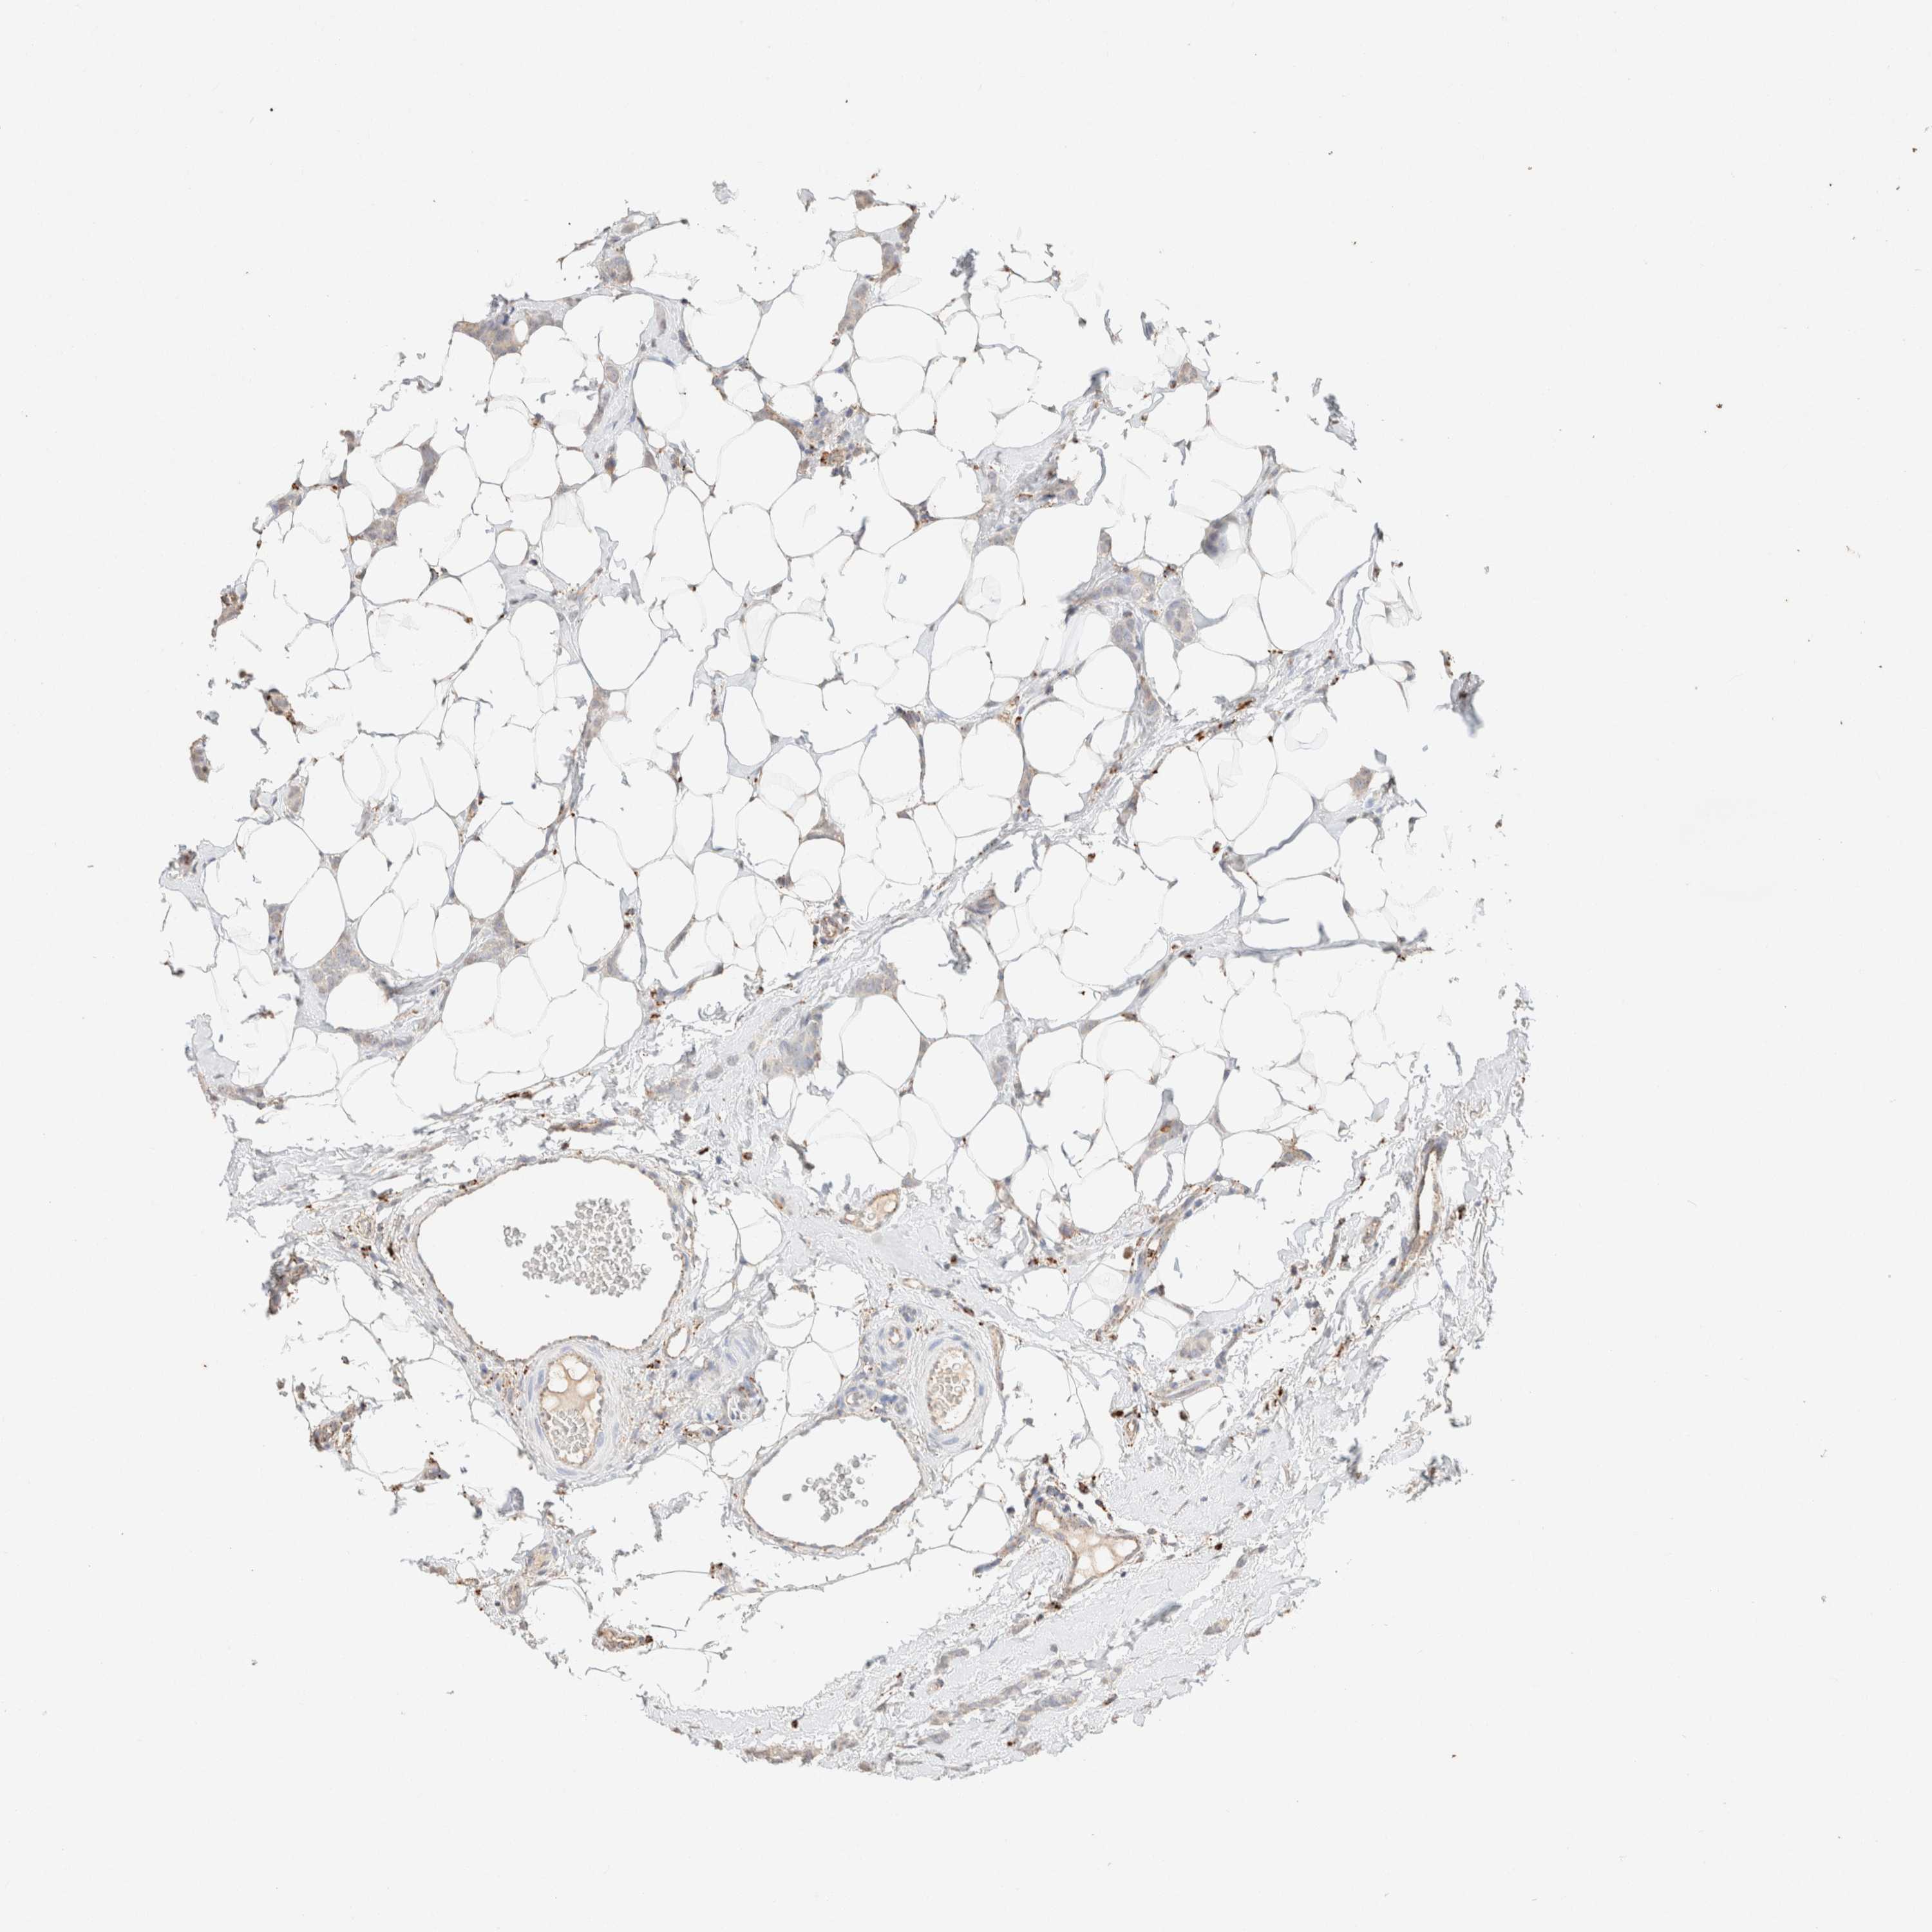

Breast cancer

Human cancer